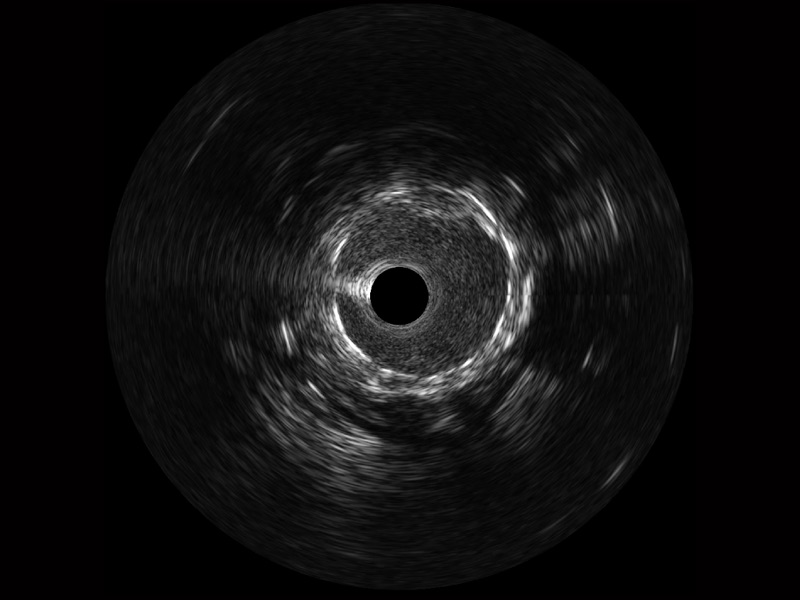

传统IVUS图像

对比传统IVUS导管成像,环球UG官网宽频IVUS图像的近场支架梁显影更细腻,远场中膜外血管仍清晰可辨,兼顾远中近,兼顾分辨力与穿透深度